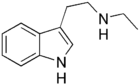

| NET | artificial | H | H | CH2CH3 | N-ethyltryptamine | 61-53-0 |